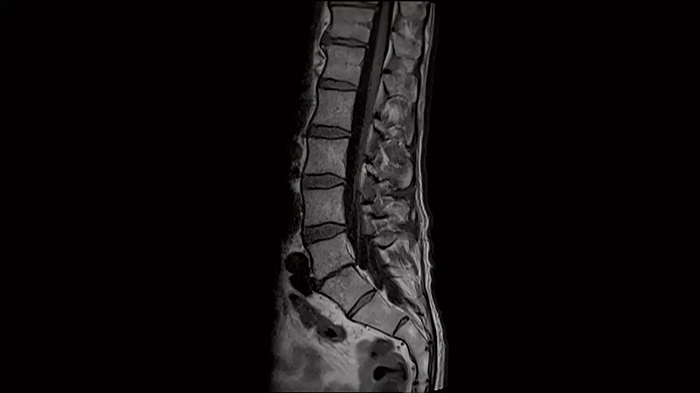

L-Spine - T1 TSE

Optimal depiction of the lower spine with T1 TSE imaging using the Spine Coil.

Image Courtesy: University Hospital Erlangen, Germany | Image-ID: 4aaaa0376